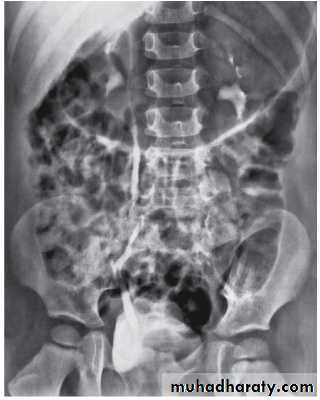

The degree of reflux is graded I–V.Grading is based on the appearance of contrast agent in the collecting system during voiding cystourethrography (VCUG(.

The VCUG:

the definitive examination

to diagnose and grade reflux and establish reversible causes

must include a voiding phase:

in some cases, reflux may be seen only during the elevated intravesical pressures associated with micturition.

in visualizing the urethra, may allow the diagnosis of outflow obstruction to be made (e.g., posterior urethral valves).

MCUG